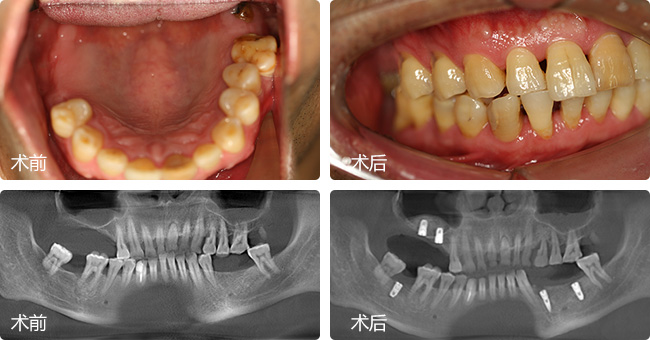

口内情况:下颌缺牙3颗,上颌缺牙2颗,合计缺牙5颗

主治医生:郑苍尚教授

种牙方案:数字化微创无痛种植 情况类似,咨询方案

种牙方案:通过德国KAVO锥形束CT检查缺牙处牙槽骨的骨质密度、厚度,并分析牙周口腔健康后,对苏伟采用“微创无痛种植”恢复牙咬合功能……[查看方案]

口腔状况:上颌缺牙2颗,下颌缺牙3颗

治疗方案:全数字化精确种植牙

主诊医生点评:根据术前CT显示的牙槽骨数据和口腔健康情况分析,微创无痛种植能有效恢复牙咬合功能,仅3-4毫米微小切口,即可完成种植,减少肿痛和出血量,种植成功率更高